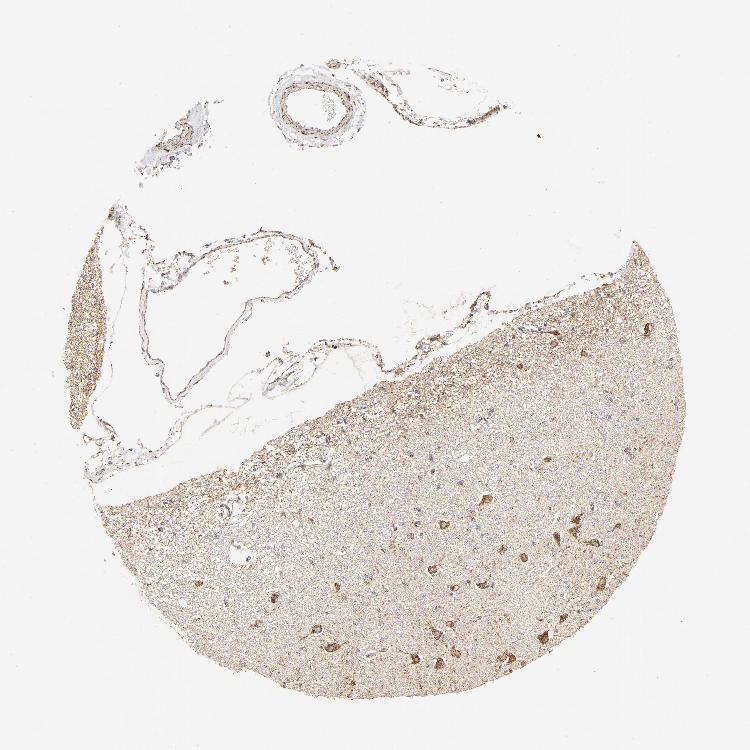

HIPPOCAMPUS - Antibody stainingi

Antibody staining in the annotated cell types in the current human tissue is reported as not detected, low, medium, or high, based on conventional immunohistochemistry profiling in selected tissues. This score is based on the combination of the staining intensity and fraction of stained cells.

Each image is clickable and will lead to virtual microscopy that enables deeper exploration of all samples and also displays staining intensity scores, fraction scores and subcellular localization as well as patient and tissue information for each sample.

Antibody HPA002076Antibody HPA003390

Glial cells Not detectedMedium